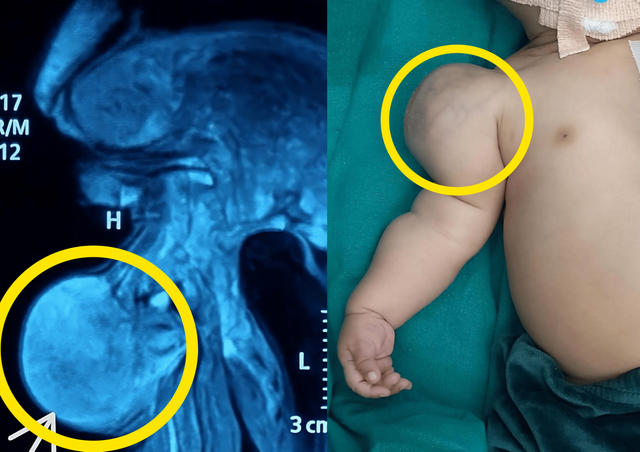

생후 한 달 된 아기의 팔에서 점점 커지는 혹이 발견됐고, 최종 진단은 저등급 영아 섬유육종이라는 희귀 악성 종양이었다.

■ 출생 직후 발견된 혹, MRI서 종양 확인

23일 의학 학술지 큐어어스(Cureus)에 따르면, 인도 로타크의 한 병원은 점진적으로 어깨 부종이 커지는 신생아 사례를 보고했다.

아이는 정상적인 자연분만으로 태어났으며, 출산 주수에도 이상은 없었다. 그러나 출생 직후부터 오른쪽 어깨에 혹이 있었고, 시간이 지나면서 점점 커졌다. 피부 위로 통증은 없었다.

자기공명영상(MRI)에서는 근육 속 연부조직에서 종양이 확인됐고, 뼈 손상은 없었다.

■ 수술로 6.5cm 종양 제거…저등급 영아 섬유육종 판정

의료진은 전신마취 하에 국소 절제술로 종양을 제거했다. 제거된 종양은 6.5cm 크기였으며, 종양 위로 또 다른 피부 막이 감싸고 있었다.

최종 조직검사 결과는 저등급 영아 섬유육종으로 나타났다. 이는 1세 미만에서 발생하는 연부조직 육종 중 가장 흔한 유형이다.